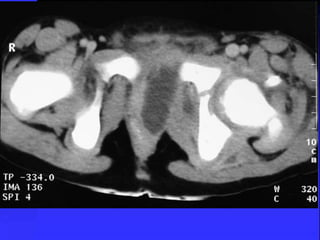

Case-5 A 3-y-oldboy presented to ER with a 10-day history of limp. with low-grade pyrexia and hx of URTI. no history of trauma. O/E: Reluctant to weight bear. Temp.: 38.5°C, Good ROM was observed in both hips. ESR:50mm, CRP: 35, normal WBCs. X-rays were normal

• 113.

Bone scan Multifocallesions in the left femur and other areas of the skeleton

• 114.

BM aspiration andtrephine biopsy showed metastatic neuroblastoma. (CT Scan ) showed a large soft tissue mass of mixed density Neuroblastoma adrenal gland.